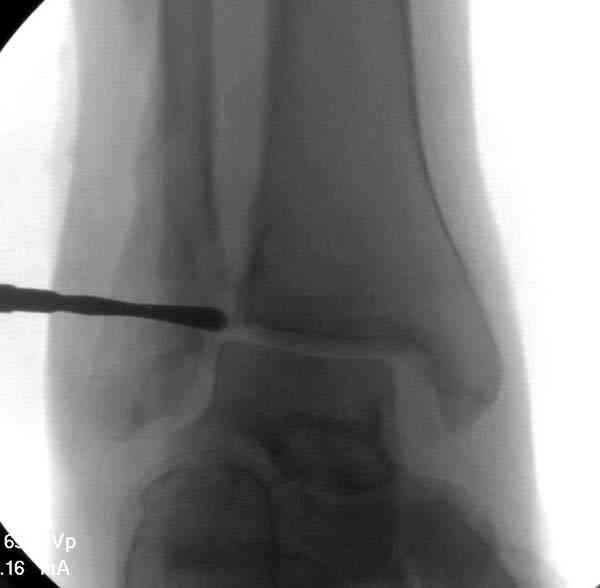

Здесь представлено решение похожей проблемы. Больной в течение года лечился консервативными мерами, и боли в голеностопе были основным показанием к операции.

Проведена обычная стандартная процедура по исправлению неудовлетворительного состояния голеностопного сустава, где кроме удлинения малоберцовой с применением compression tension device за проксимальный конец пластины, проведено замещение трикортикальным графтом из крыла, освобождение синдесмоза и медиальной щели от

фибротических масс с фиксацией.